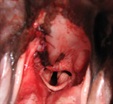

Rozštěp patra (vysvětlivky u obr. 1)

bílá šipka: měkké patro

zelená linka - okraj rozštěpu

modrá šipka ukazuje, které 2 okraje mají být spojené

žlutá šipka - tudy se dostává potrava do nosní dutiny